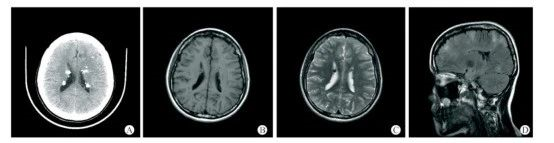

19岁女性结节性硬化症患者的头颅CT+MRI平扫影像[6]

患者临床表现为癫痫及精神发育异常,右面部色素沉积斑、四肢及躯干多发色素脱失斑、双侧峡部皮脂腺瘤,胸椎多发斑片状致密影。A-C:头颅CT+MRI平扫示双侧室管膜下及皮层下多发结节样钙化灶;D:T2FLAIR示大脑半球皮层及皮层下多发异常高信号影。